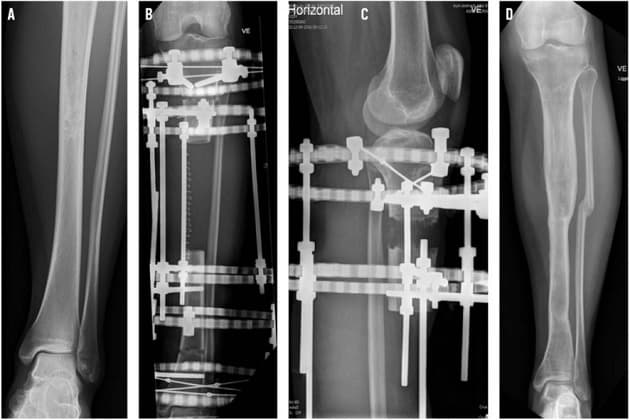

FIGUR 3 / A. Adamantinom i tibia præoperativt. B. Ringfiksation af knogledefekt efter tumorresektion. C. Knoglenydannelse. D. Postoperativt resultat med knogleopheling.